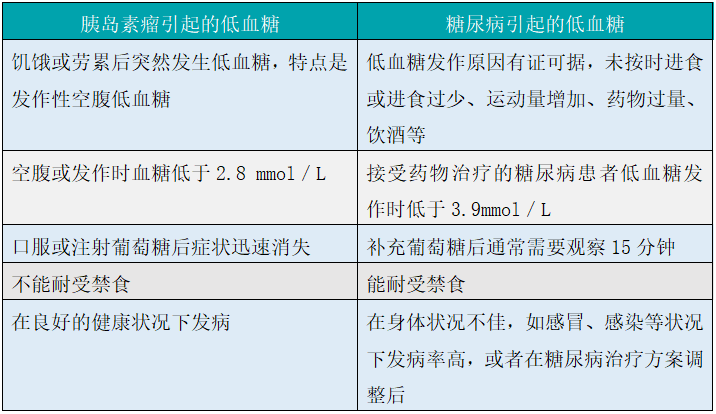

胰岛素瘤和糖尿病引起的低血糖区别

糖尿病:

I型糖尿病:多于青少年发病,体内可检测到胰岛素抗体及胰岛素受体抗体、I型糖尿病相关抗体;胰岛素绝对不足,有酮症倾向,需检测胰岛素和相关抗体检测。

药物性糖尿病:某些药物可引起胰岛β细胞功能异常导致胰岛素分泌不足出现糖代谢紊乱,本患者无相关药物史,暂不考虑此病。

内分泌性糖尿病:多见于内分泌疾病患者,如肢端肥大症、Cushing综合征、嗜铬细胞瘤、甲状腺功能亢进症时诱发血糖水平升高,该患者无上述病史,暂不考虑此病。